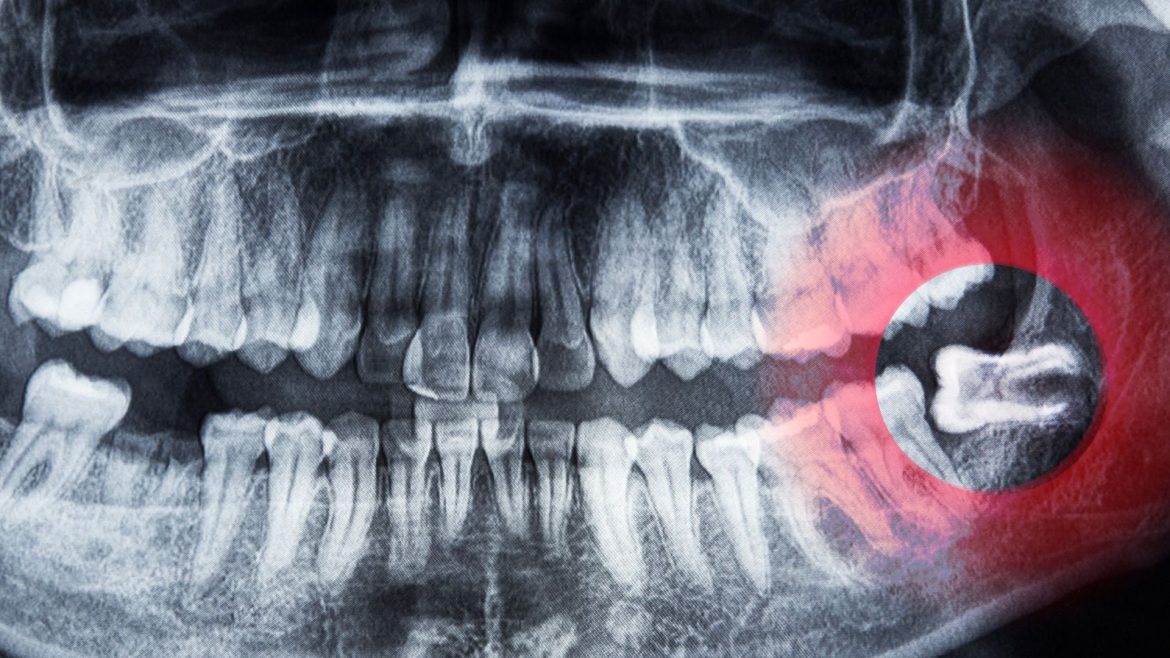

Trám răng thẩm mỹ không chỉ hữu ích trong việc khắc phục lại tính hoàn thiện cho răng bị mẻ mà còn vô cùng hữu ích trong việc điều trị răng sâu hay răng bị mẻ. Mặc dù đây là …